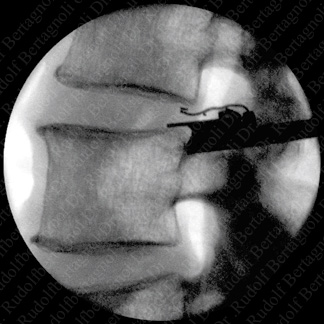

The Barricaid® is designed for quick and safe implantation following limited discectomy. In clinical cases performed to date, surgeons have successfully implanted the Barricaid in just minutes. To the left one can see a template being used to properly size the implant. |